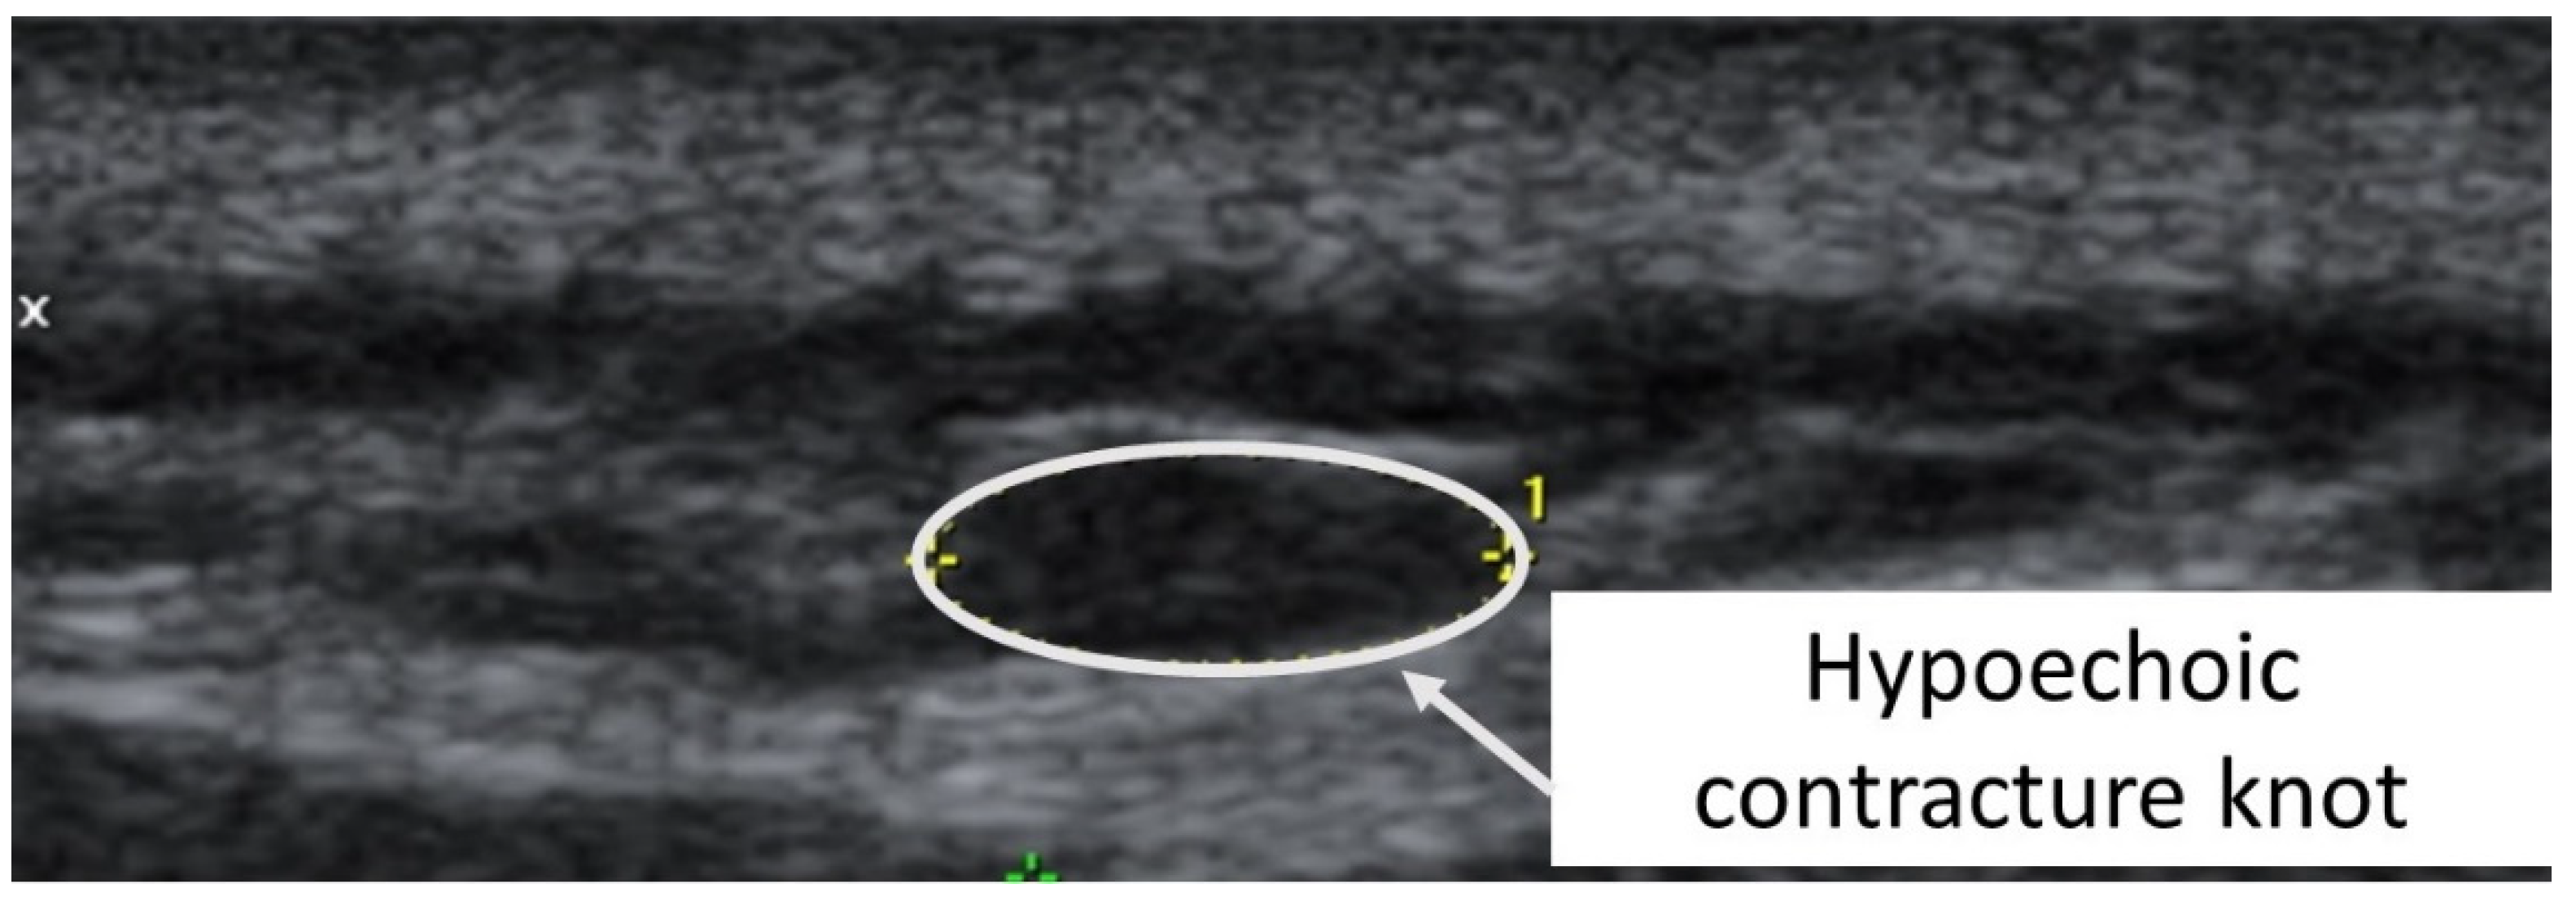

A taut band with a palpable nodule within the medial gastrocnemius was identified as responsible for his right plantar heel pain symptoms [32]. As had been the case with previous bouts of plantar pain, the subject reported, upon palpation, a pain referral symptomatology into the plantar aspect of his foot as his pain symptoms (pain recognition). The nodule was subsequently imaged in long-axis with a Siemens Acuson S200 Ultrasound system (Siemens, Munich, Germany) with an 18L6 16 Hz high-definition linear probe. A large hypoechoic contracture knot (109 mm × 47 mm) was identified (Figure 1) with smaller hyperechoic “speckles” (Figure 2) within the hypoechoic contracture knot.

Figure 1.

Ultrasound imaging assessment of the right gastrocnemius muscle showing the palpable contracture knot as a hypoechoic (hyperperfused) area.